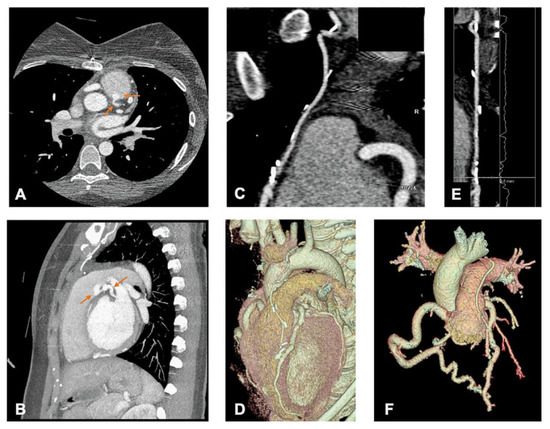

Chest Pain After Surgical Repair of Bland-Garland-White Syndrome

by André Azul Freitas, Rui Baptista, Valdirene Gonçalves, Nuno Campos and Lino Gonçalves

Cardiovasc. Med. 2022, 25(1), 60; https://doi.org/10.4414/cvm.2022.02191 - 1 Jan 2022

A 19-year-old female with a past history of a surgical correction of a Bland-Garland-White syndrome was admitted to the emergency department complaining of chest pain precipitated by exercise [...] Full article

Show Figures

Figure 1